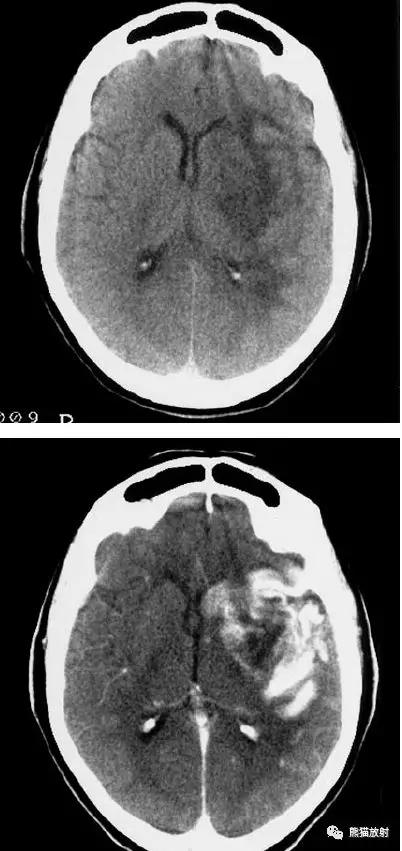

出血性脑梗死

上矢状窦血栓形成,呈高密度(箭头);并邻近脑实质内出血性脑梗死。